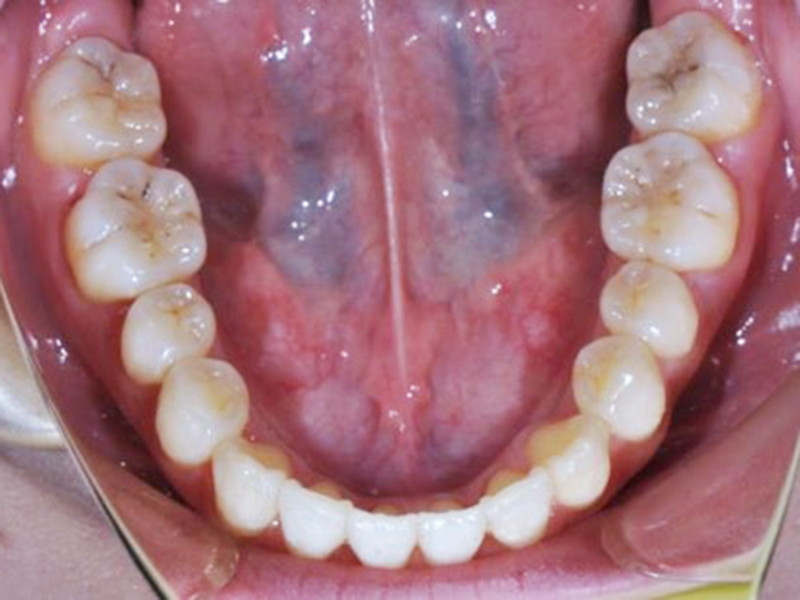

before

経過